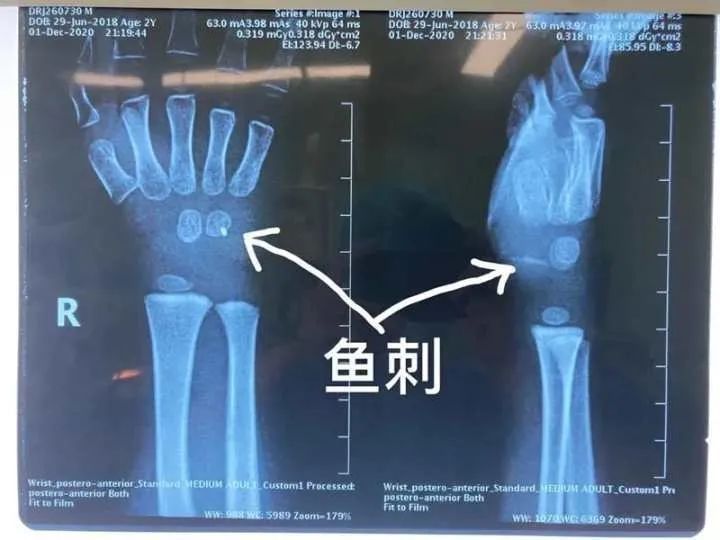

近日,杭州市儿童医院 骨科就接诊了一位 被鱼刺扎伤手腕 的小患者 原来,调皮的元元(化名) 在家拿着鱼玩耍 结果不小心忽然摔倒 鱼刺深深地扎进了他的手腕

由于伤口情况复杂 辗转多家医院均无法手术 最后来到了杭州市儿童医院骨科 拍片检查后发现

鱼刺已经深及元元的手腕内部约一厘米左右的位置虽然体表伤口细小但是内部伤口附近神经血管交织错杂 如不及时取出鱼刺 会严重影响孩子的手腕功能

手术室里骨科医生采用C臂机仔细定位后探查鱼刺 发现鱼刺像一把锋利的小匕首 切断了肌肉和腕横韧带,刺入到腕管内毗邻正中神经和肌腱,并且鱼刺已断成两截这无疑大大增加了取出的难度在小心翼翼地取出鱼刺后医生再次探查周围神经、血管、肌腱确定没有残留及其他损伤 经过两个多小时 终于为孩子解决这恼人的“不速之客”